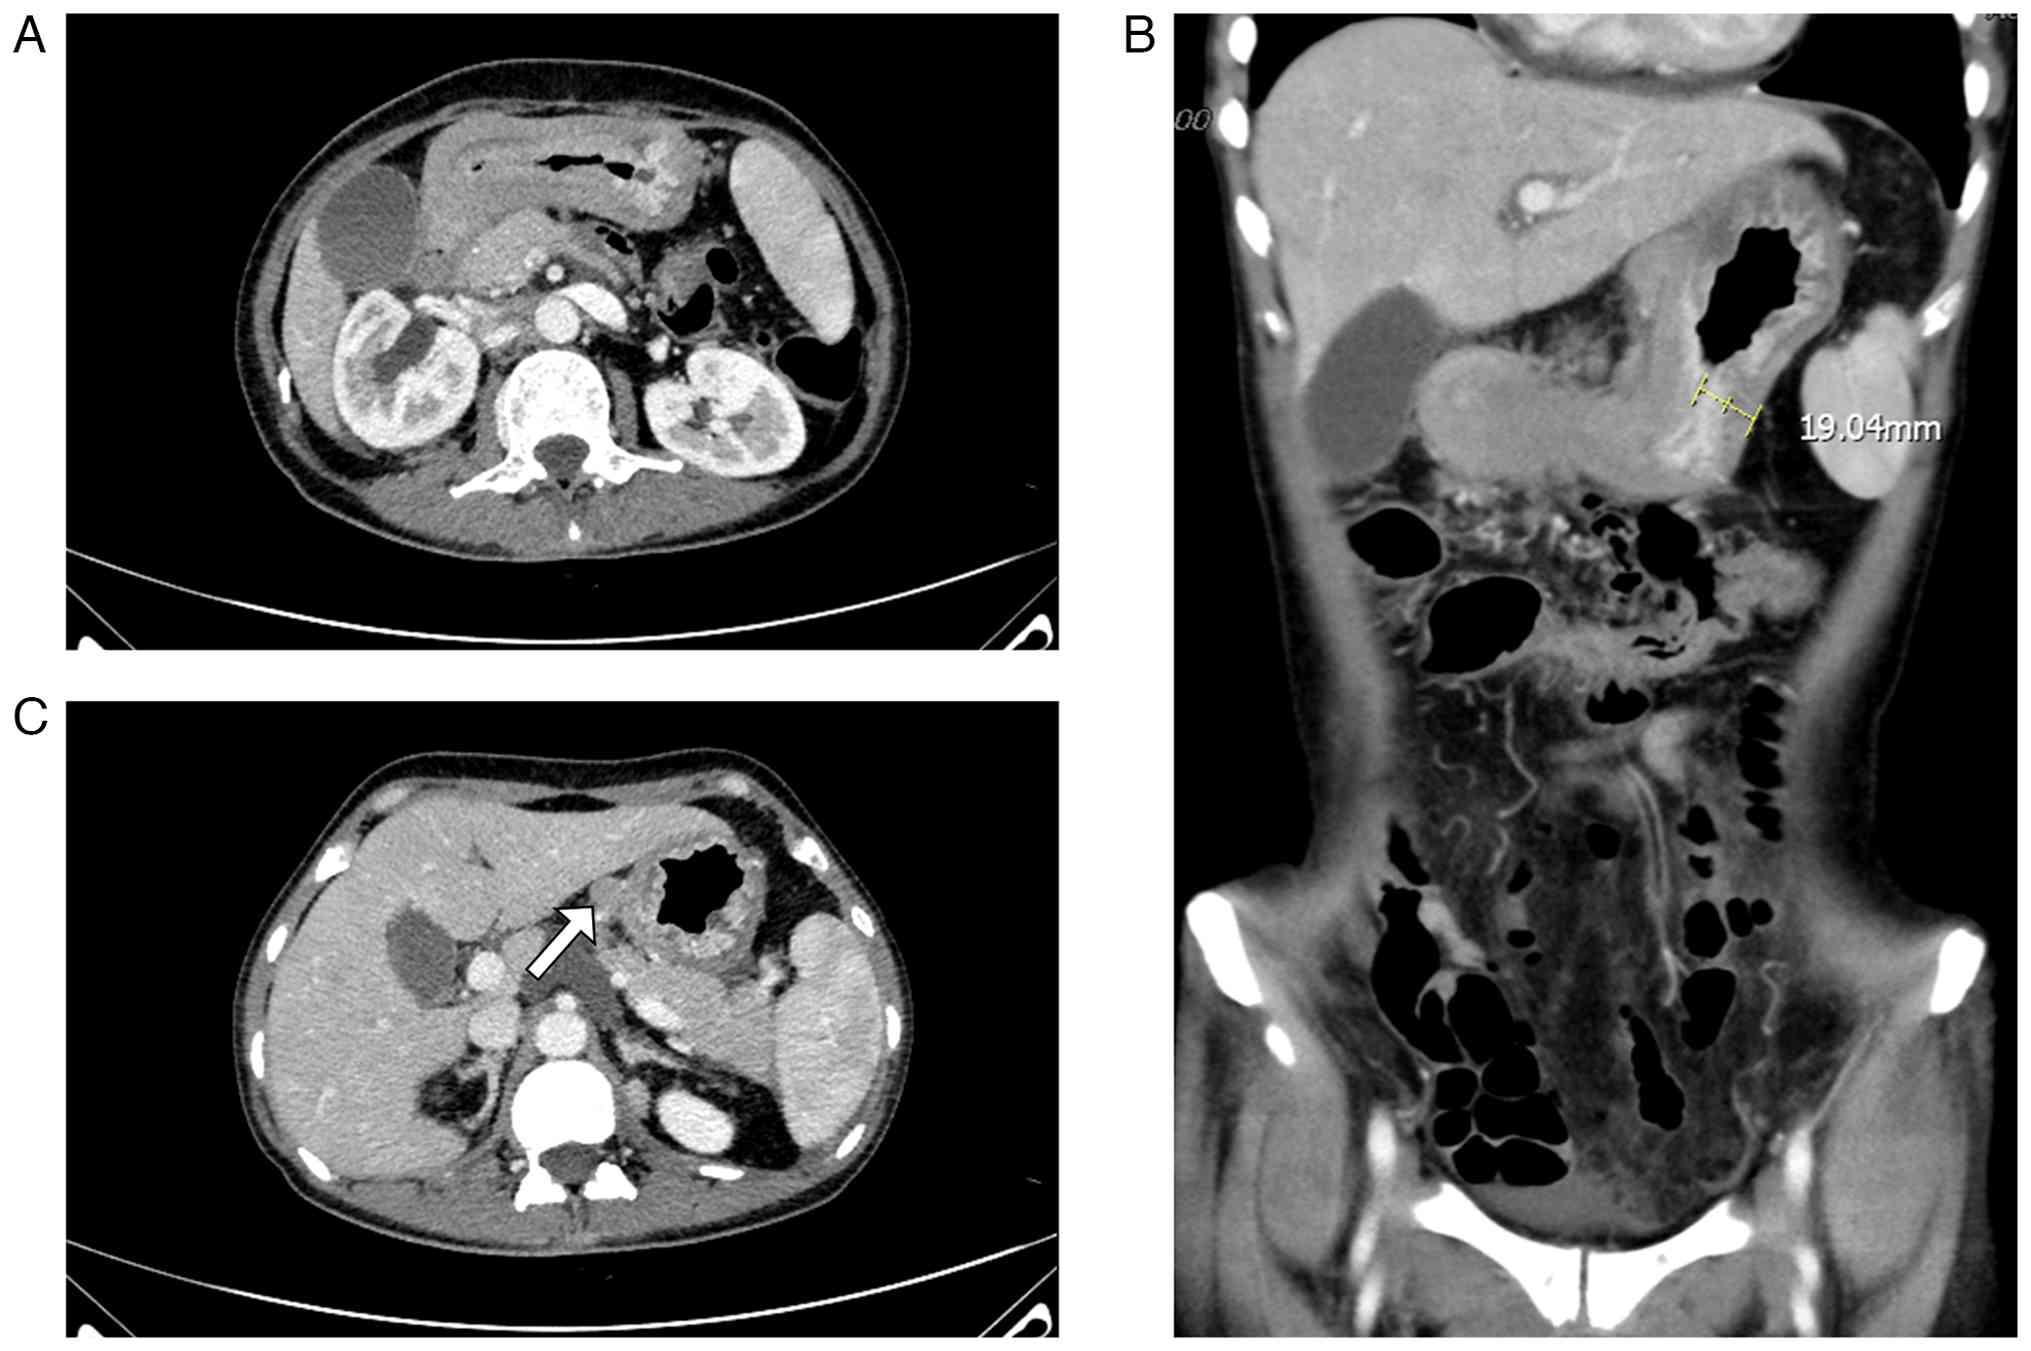

The patient was admitted to The General Hospital of Western Theater Command in January 2022 due to persistent symptoms. At admission, an Eastern Cooperative Oncology Group performance status of 2 was reported (8). The patient reported notable weight loss of ~6 kg across the preceding 2 months. Laboratory investigations revealed mild anemia (97 g/l; reference range, 115-150 g/l), hypokalemia (3.29 mmol/l; reference range, 3.5-5.3 mmol/l) and hypoalbuminemia (28 g/l; reference range, 35-52 g/l). Tumor markers were notably elevated, with carcinoembryonic antigen (CEA) at 219.74 ng/ml (reference value, <5 ng/ml), carbohydrate antigen (CA)125 at 124.90 U/ml (reference value, <35 U/ml) and CA15-3 at 146.30 U/ml (reference value, <25 U/ml). A longitudinal assessment of tumor markers (Fig. S4) demonstrated dynamic changes in serum CEA, CA125 and CA15-3 levels from the diagnosis of bone metastasis in December 2019 to the presentation of peritoneal disease in January 2022, which was associated with disease progression. A physical examination revealed notable abdominal distension, with no palpable mass detected in the left breast. Contrast-enhanced abdominal CT performed in January 2022 demonstrated marked circumferential wall thickening (maximum thickness 16.05 mm; Fig. 2C) extending from the gastric antrum to the pylorus, with heterogeneous attenuation, accompanied by notable gastric distension and fluid retention, consistent with pyloric obstruction and gastrostasis. Although these findings were consistent with gastrostasis, the primary clinical presentation was dominated by symptoms of functional gastric outlet obstruction, initially suggesting a gastroparesis-like mechanism rather than a fixed mechanical obstruction (Fig. 2). Gastroscopy performed in January 2022 revealed edema and narrowing in the gastric body and antrum (Fig. 3A-C). Given the poor nutritional status of the patient, a nasojejunal tube was placed under ultrathin gastroscopic guidance and biopsies were obtained. Histopathological examination of the gastric mucosal biopsies on routine sections showed only chronic superficial gastritis (Fig. 3D). The initial endoscopic biopsy was therefore considered non-diagnostic for malignancy.

Contrast-enhanced abdominal CT

findings at initial presentation with abdominal symptoms. (A) Axial

CT image demonstrates marked gastric distension with intragastric

fluid retention, consistent with gastrostasis. (B) Coronal CT image

shows circumferential wall thickening extending from the gastric

antrum to the pylorus (arrow), with heterogeneous attenuation; the

maximum wall thickness is ~16.05 mm. (C) Additional axial CT image

again demonstrates marked gastric distension and fluid retention,

consistent with pyloric obstruction and gastrostasis.

Figure 2

Contrast-enhanced abdominal CT findings at initial presentation with abdominal symptoms. (A) Axial CT image demonstrates marked gastric distension with intragastric fluid retention, consistent with gastrostasis. (B) Coronal CT image shows circumferential wall thickening extending from the gastric antrum to the pylorus (arrow), with heterogeneous attenuation; the maximum wall thickness is ~16.05 mm. (C) Additional axial CT image again demonstrates marked gastric distension and fluid retention, consistent with pyloric obstruction and gastrostasis.